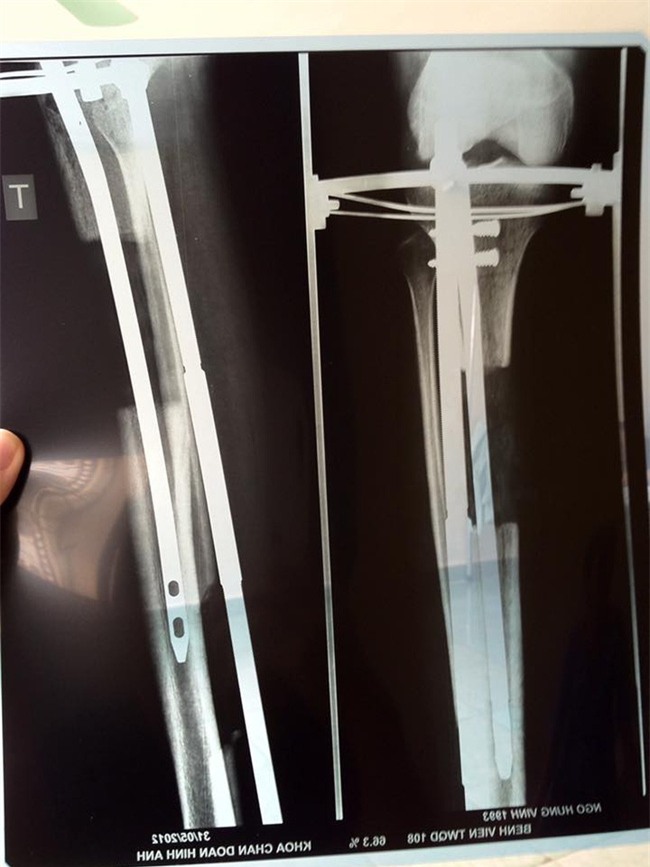

Bước 1: phẫu thuật đóng đinh nội tuỷ và lắp khung

Bước 2: thời kì tự căn giãn xương tại nhà ( dưới sự chỉ dẫn của bác sĩ) tái khám và chụp X-quang 3 tuần/lần.

Bước 3 : cố định đinh nội tuỷ và tháo khung

Đây là một số hình ảnh trong và sau thời kì thực hiện phương pháp kéo dài chi của Tùng Anh được cậu chia sẻ kèm theo bài viết.